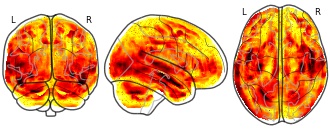

Brain volumetric changes in the general population following the COVID-19...

EmailClick to copy linkLink copied Cite(2020). Brain volumetric changes in the general population following the COVID-19 outbreak and lockdown: Volumetric changes: lockdown test group versus control group (whole brain) [Dataset]. http://identifiers.org/neurovault.image:404834niftiAvailable download formatsUnique identifierhttps://identifiers.org/neurovault.image:404834Dataset updatedSep 7, 2020License

Cite(2020). Brain volumetric changes in the general population following the COVID-19 outbreak and lockdown: Volumetric changes: lockdown test group versus control group (whole brain) [Dataset]. http://identifiers.org/neurovault.image:404834niftiAvailable download formatsUnique identifierhttps://identifiers.org/neurovault.image:404834Dataset updatedSep 7, 2020LicenseCC0 1.0 Universal Public Domain Dedicationhttps://creativecommons.org/publicdomain/zero/1.0/

COVID-19 pandemic led to severe health and financial conditions worldwide. As an attempt to reduce the pandemic spread, most countries followed a lockdown policy albeit its devastating financial cost. It was generally reported, during and after the lockdown period, on an increase in anxiety and stress among the population. In the current study, we explored the manifestations of this period on the brain structure. Hypothesizing that the lockdown period might have induced stress-related brain modification, we examined volumetric changes in N = 100 participants scanned in two time-points. We examined the neural changes observed in n = 50 participants scanned before and after the lockdown period, and compared these changes to a control group of n = 50 participants that were scanned twice before the lockdown.

TwitterBrain volumetric changes in the general population following the COVID-19 outbreak and lockdown: Volumetric changes: lockdown test group versus control group (whole brain)

COVID-19 pandemic led to severe health and financial conditions worldwide. As an attempt to reduce the pandemic spread, most countries followed a lockdown policy albeit its devastating financial cost. It was generally reported, during and after the lockdown period, on an increase in anxiety and stress among the population. In the current study, we explored the manifestations of this period on the brain structure. Hypothesizing that the lockdown period might have induced stress-related brain modification, we examined volumetric changes in N = 100 participants scanned in two time-points. We examined the neural changes observed in n = 50 participants scanned before and after the lockdown period, and compared these changes to a control group of n = 50 participants that were scanned twice before the lockdown.